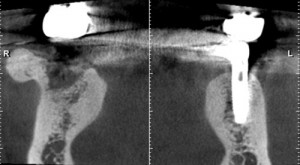

虫歯で抜歯になり、抜歯後6カ月のCT画像。なんだか、穴が開いたままで、ちっとも骨で埋まっていないように、見えた(緑→)。うっすらと、骨の蓋ができているようにも見える(黄→)が、当院の伊藤医師とも相談し、外側に突き出ている骨の出っ張り(ピンク→)をとって、穴を埋める事を念頭に入れて手術を開始した。

結果は、骨の蓋ができており、通常通りインプラントが入れられた。骨の出っ張りは、患者さんは元々気にされていなかったので、そのままにした。骨が出っ張る原因は歯ぎしりが考えられている。インプラントに被せ物が入った後は、歯ぎしり防止用のマウスピースがあったほうがいい。青→は私が17年前に入れた初期のタイプのインプラント。まだ、もっている。(長谷川)

下顎輪切りCT画像 R(患者さんにとっての右)L(患者さんにとっての左)緑→(骨密度の低い部分、一見穴になっているように見える)黄→(穴をふさぐようにできている骨のふた)ピンク→(骨のでっぱり)青→(インプラント)